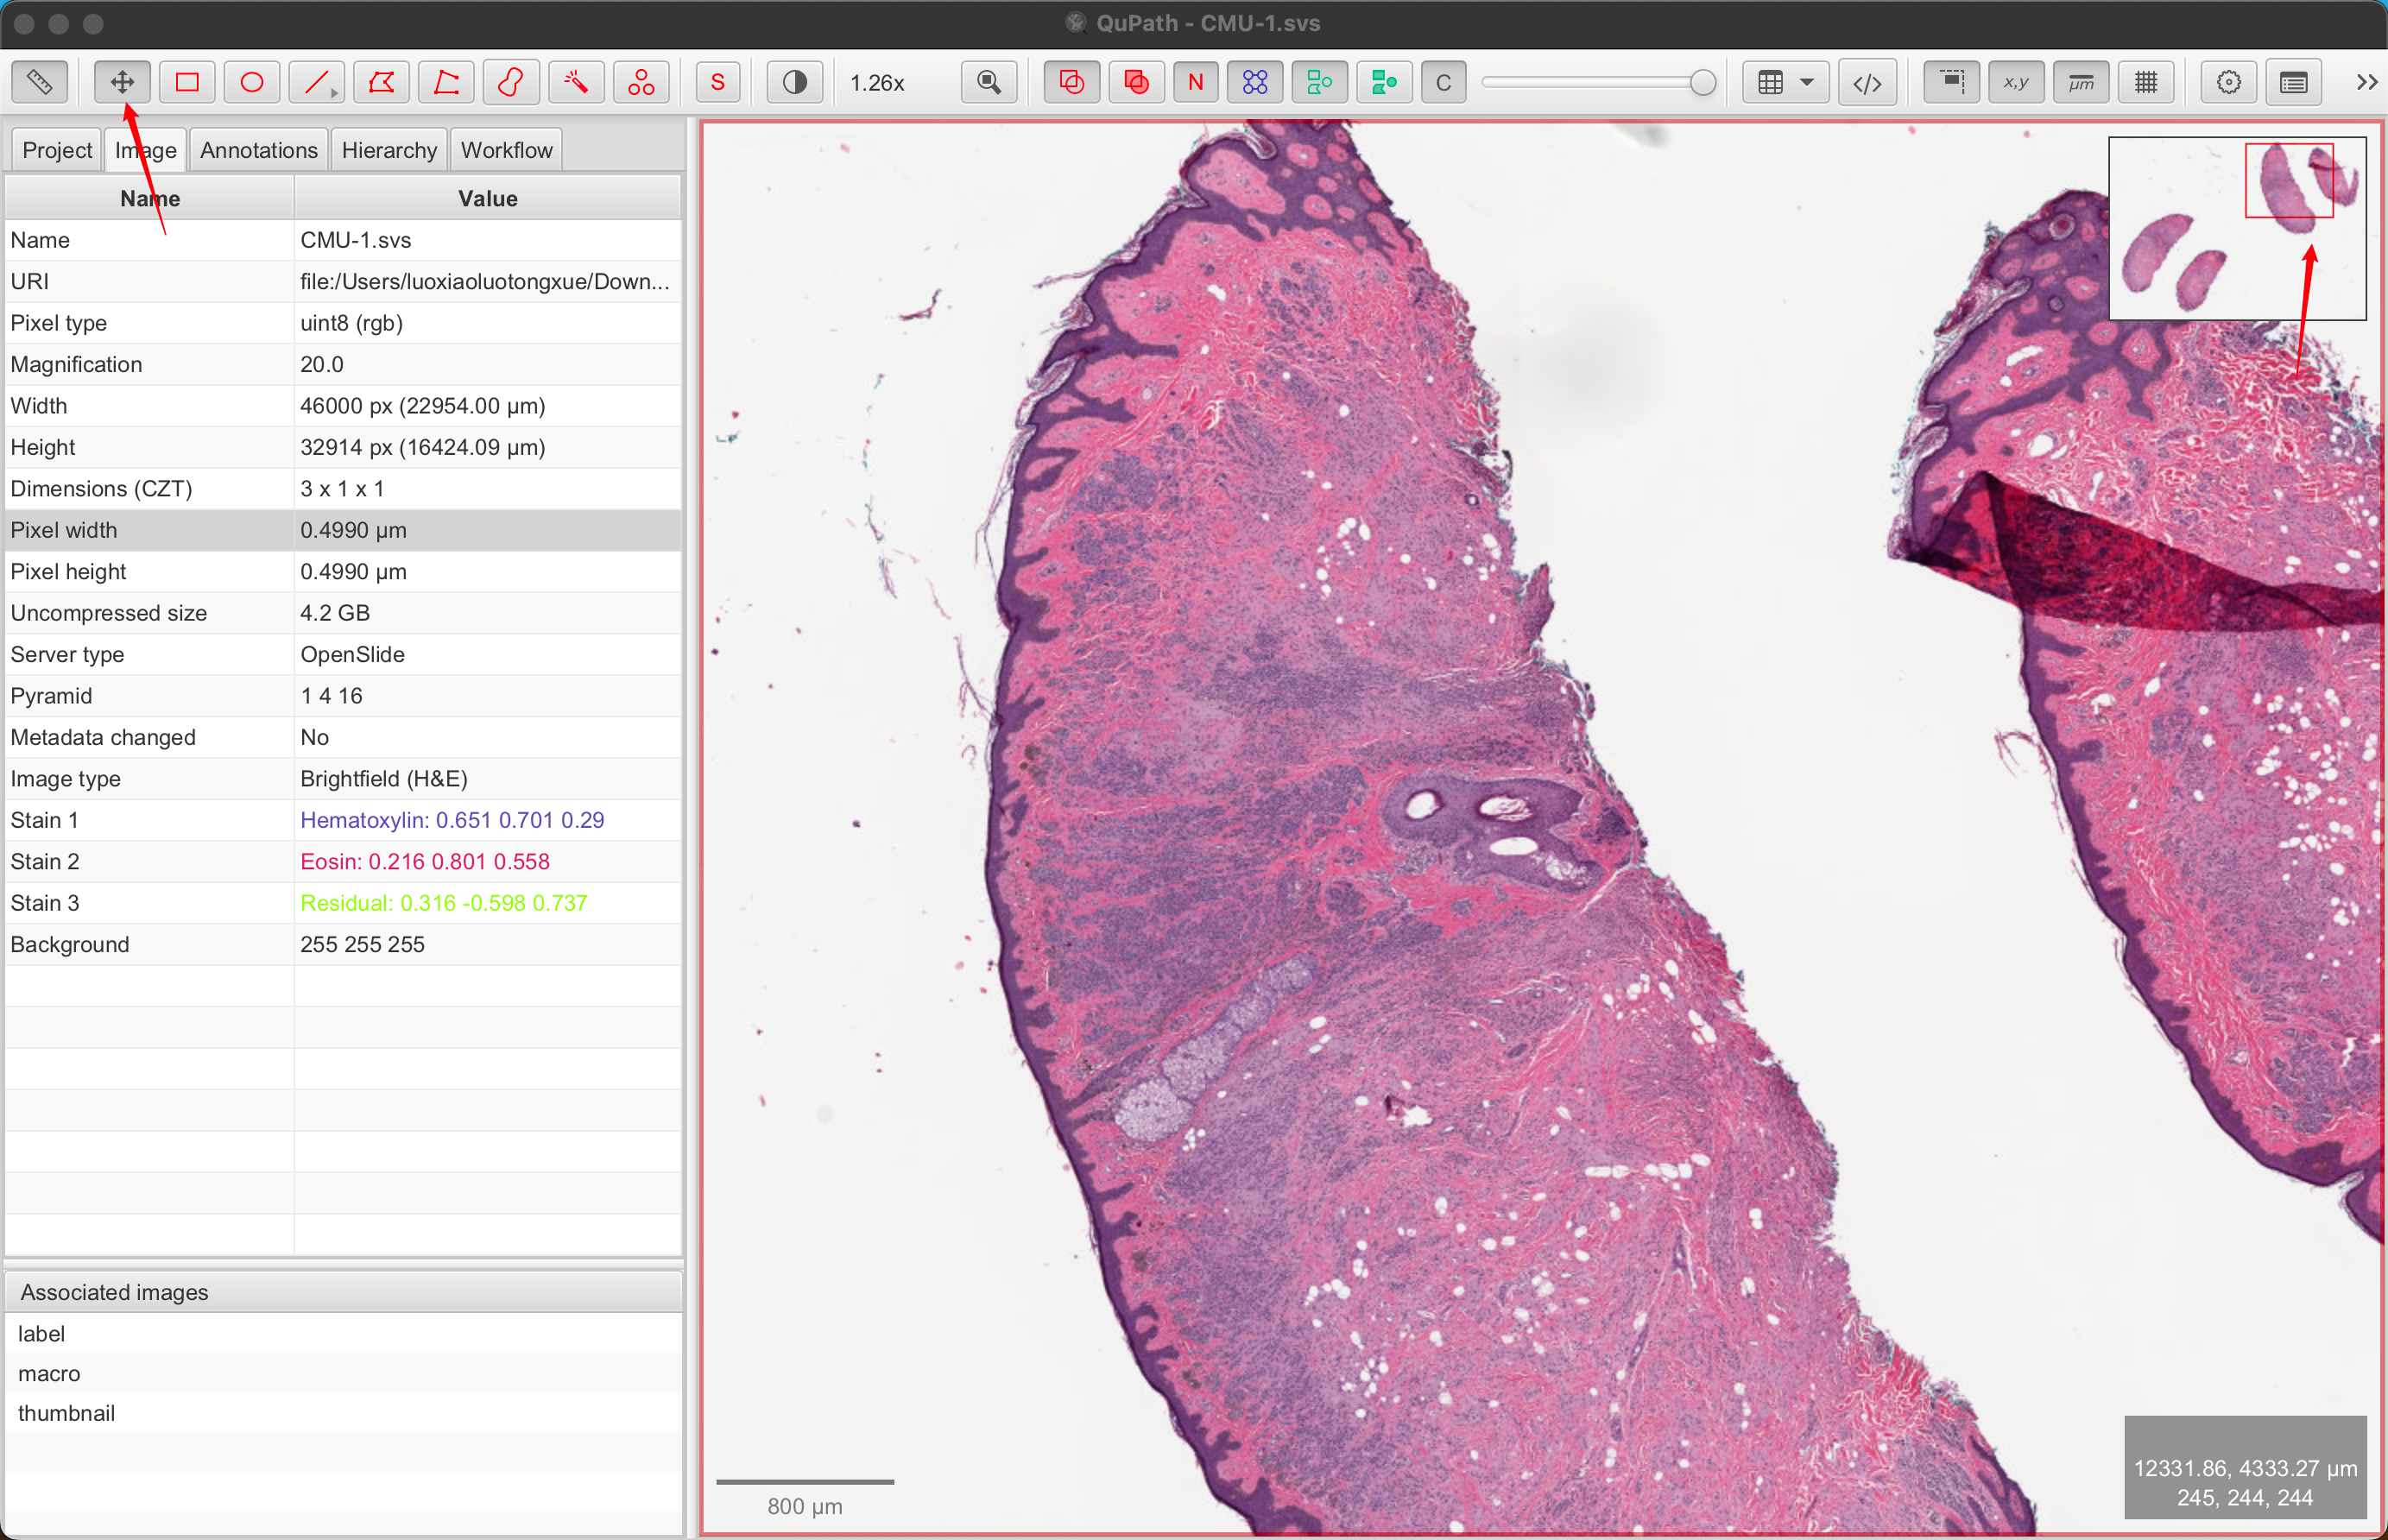

1-3:查看图像属性

通常,QuPath 窗口左侧有一个面板:分析面板。如果没有,请单击工具栏上的分析面板按钮将其打开。

这里有几个选项卡,您稍后会遇到。现在,单击**“图像”**选项卡以获取与您的图像相关的属性表。

1-4:设置像素大小

如果存储在图像文件中,QuPath 应自动获取像素大小并将其显示在**“图像”**选项卡(“像素宽度”和“像素高度”)下。

如果没有,您可以通过双击任一行并输入正确的值来手动设置像素大小。